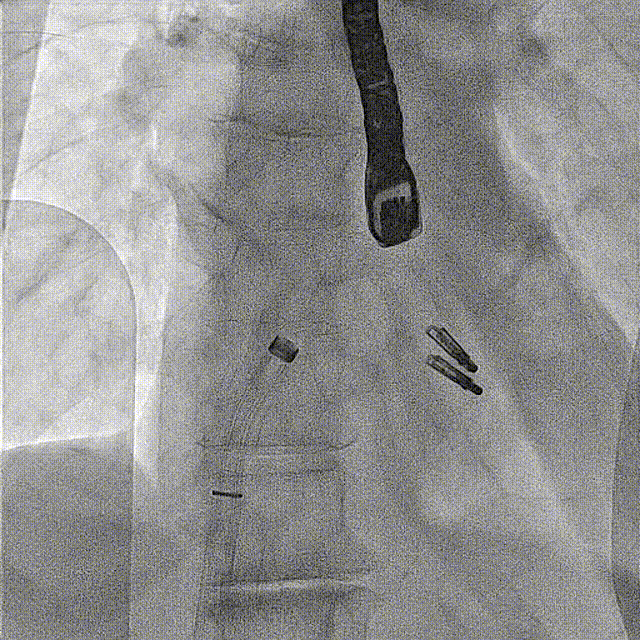

DSA提示双夹稳定